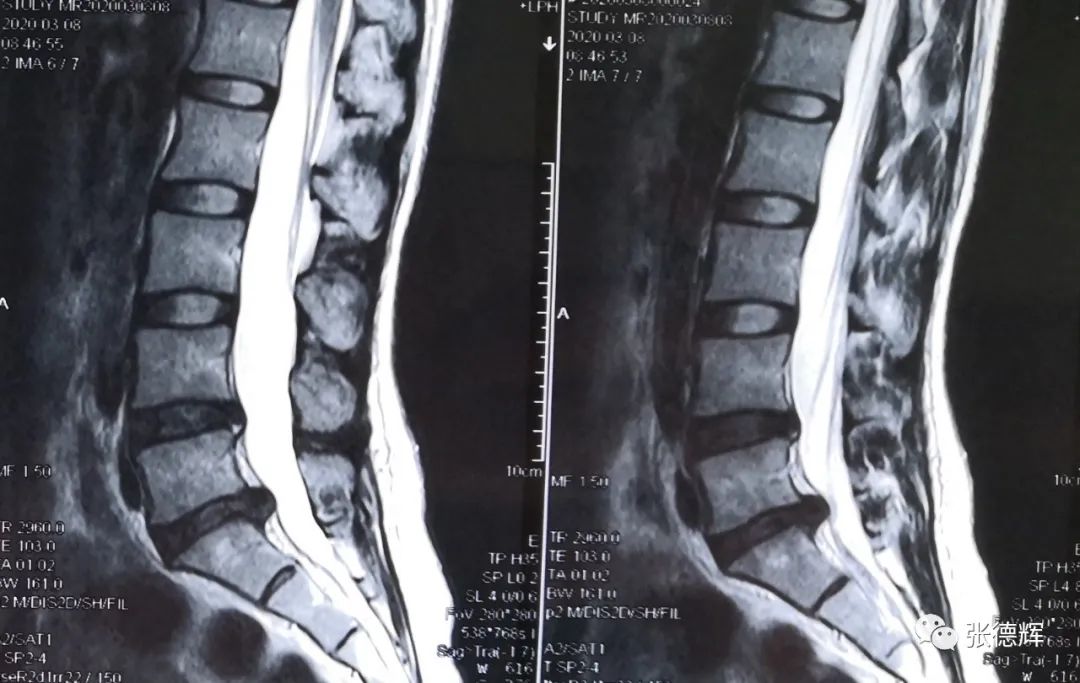

腰椎核磁共振检查,矢状位片提示腰5-骶1椎间盘突出,横断位片可见突出物位于神经根腋下